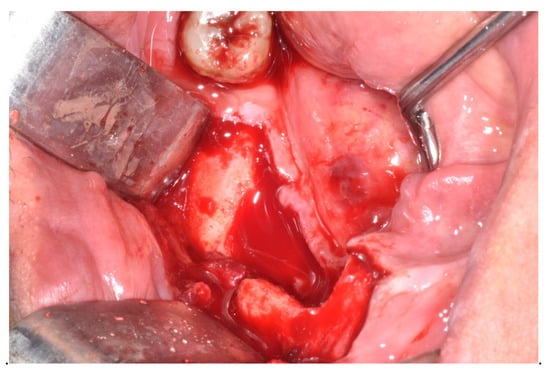

| Treatment | ||||||||

| Surgical | x | x | x | 3 | 10 | |||

| Sequestrectomy | x | 1 | 1 | |||||

| Submarginal resection | x | x | 2 | 3 | ||||